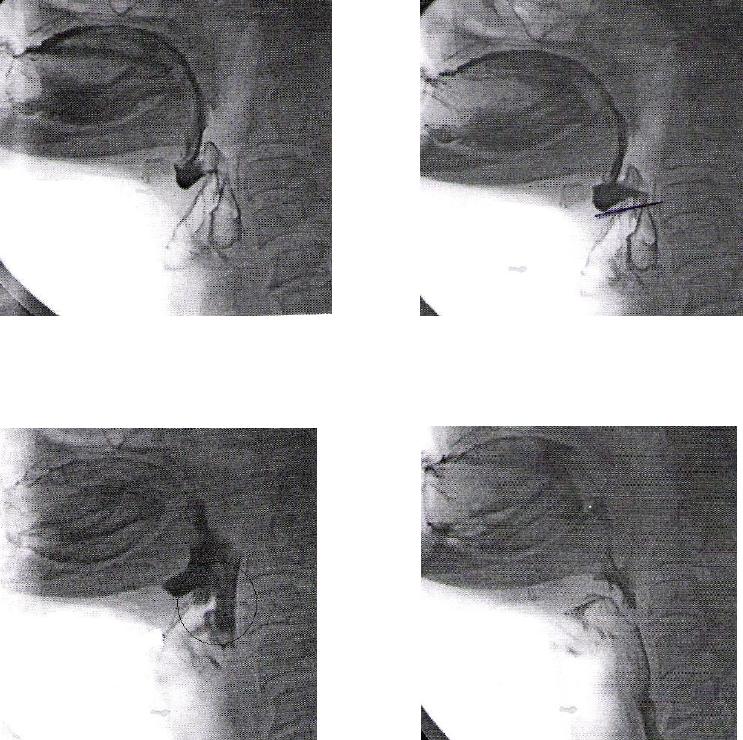

ANEXO E Imagens videofluoroscópicas da deglutição, registrando

escape prematuro e reação de deglutição atrasada, p e s

crioestimulação, com líquido e pastoso.........................................................